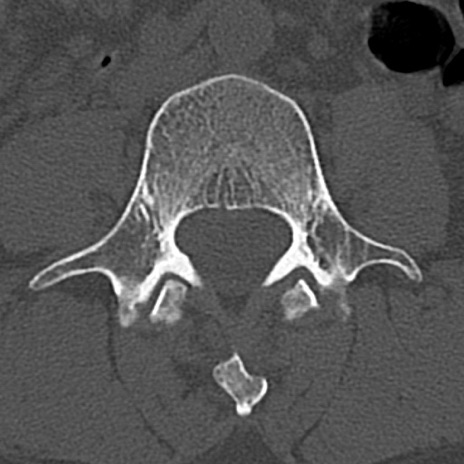

腰椎CT

横断像と矢状断像